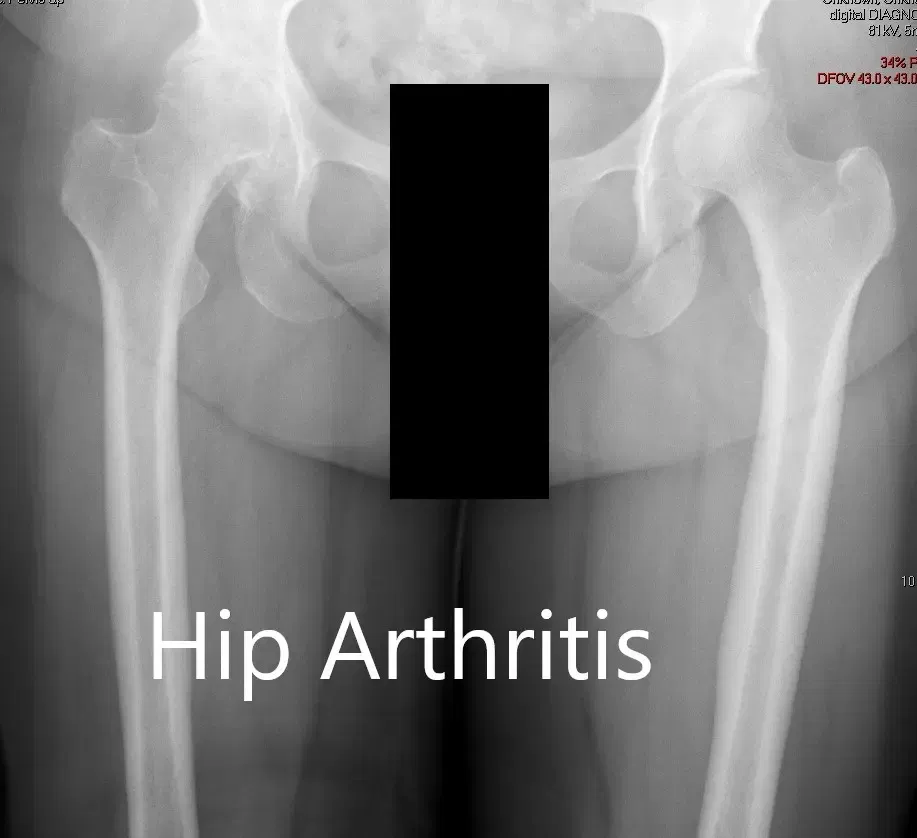

There was no distal neurological deficit. The distal extremity pulses were good volume and palpable. There was a linear scar over the right knee consistent with a previous right knee replacement. Imaging studies revealed severe osteoarthritis of the right hip.

Preoperative X-ray showing the AP view of the pelvis with both hip joints

Preoperative X-ray showing the AP and the frog-legged lateral view of the right hip